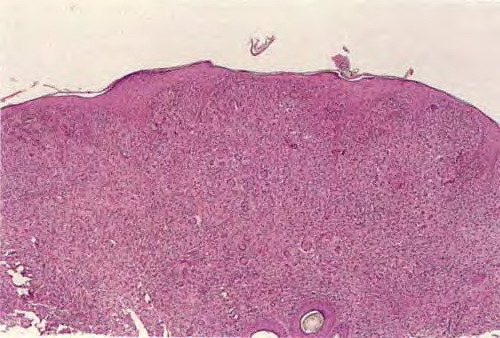

Biopsy sections of JXG lesions show a feature that is common to many NLCHs, that is, a nonepidermotropic histiocytic infiltrate lacking Langerhans granules. Early lesions of JXG are characterized by a monomorphous, non-lipid-containing histiocytic infiltrate that occupies at least the upper half, and sometimes the entire thickness, of the dermis. Mature lesions

contain foam cells, foreign-body giant cells, and Touton giant cells, mainly distributed in the superficial dermis and on the border of the infiltrate. Lymphocytes, eosinophils, and neutrophils are variably associated. Older lesions may show fibrosis. In mature lesions, fat stains yield positive results. The majority of JXG lesional biopsy sections stain positive for CD68/Ki-M1P and factor XIIIa but negative for CD1a and S100 protein.